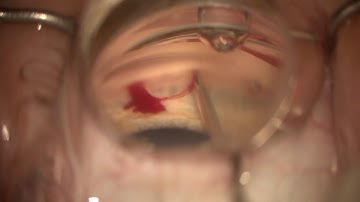

iStent inject W 1st case